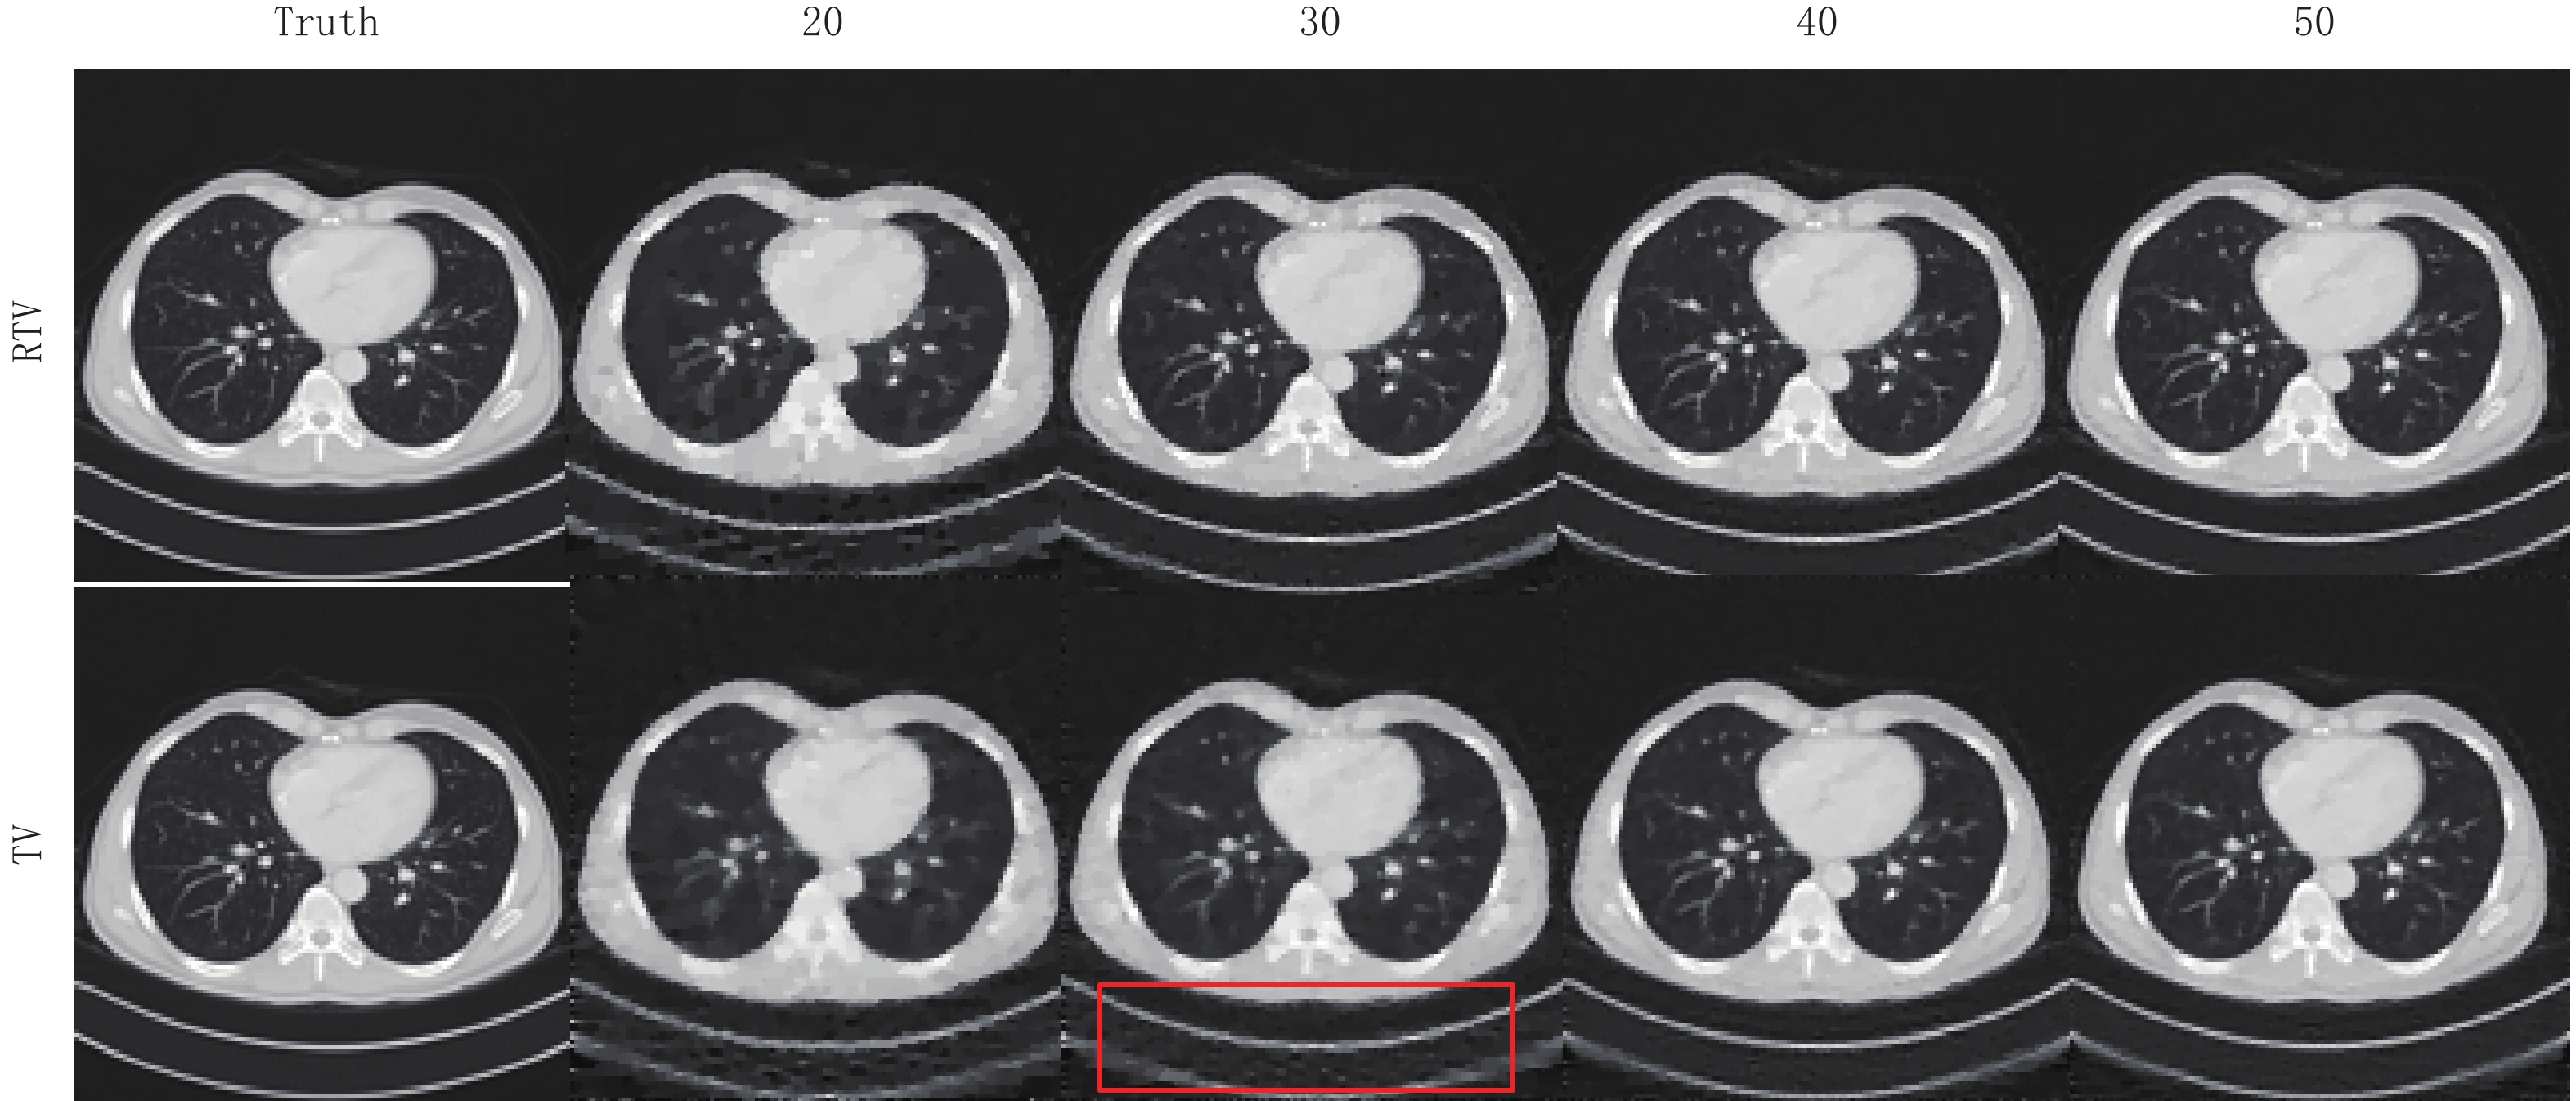

为了评估RTV算法的稀疏重建能力,本节实验分别使用RTV算法和TV算法对FORBILD、Shepp-Logan和真实CT图像模体在20,30,40,50个投影角度下进行模拟实验。这些模体的大小都是128

表 1 RTV算法和TV算法重建FORBILD模体的RMSE和SSIM比较Table 1. RMSE and SSIM comparison of RTV and TV algorithms for FORBILD phantom reconstruction项目 算法 投影个数 20 30 40 50 RMSE RTV 30.0×10-5 9.96×10-5 7.11×10-5 5.60×10-5 TV 5130×10-5 2530×10-5 620×10-5 590×10-5 SSIM RTV 0.9587 0.9792 0.9972 0.9992 TV 0.9293 0.9583 0.9943 0.9986 图7显示了两种算法关于FORBILD模体的重建结果。在20个投影角度下,TV算法重建结果有明显的伪影和噪点,并且有多处图像细节也被平滑掉。从20个到50个投影角度,其重建图像的精度虽然不断升高,不过一直到50个投影角度时,其重建图像与原图相比还是有些明显的伪影。而同样在20个投影角度的情况下,RTV最小化算法重建结果用肉眼几乎看不出与原图的区别。随着投影角度的增加,其重建结果与原图相比还是一致的。显然RTV算法的重建效果更好一点。

图8显示了两种算法关于Shepp-Logan模体的重建结果,通过对比,可见在20个投影角度下,RTV最小化重建算法的重建结果与原图相比用肉眼几乎看不出与原图的区别。而TV最小化算法在20个投影角度下的重建结果对于图像结构的保护还是有所欠缺,模糊了较多的细节。但随着投影角度的增加,其重建精度也越来越高,两种算法的重建结果与原图相比都几乎一样。

表 2 RTV算法和TV算法重建Shepp-Logan模体的RMSE和SSIM比较Table 2. RMSE and SSIM comparison of the RTV and TV algorithms for Shepp-Logan phantom reconstruction项目 算法 投影个数 20 30 40 50 RMSE RTV 8.010×10-5 4.791×10-5 3.349×10-5 2.586×10-5 TV 1610×10-5 530×10-5 160×10-5 80×10-5 SSIM RTV 0.9866 0.9948 0.9978 0.9995 TV 0.9812 0.9923 0.9956 0.9991 图9显示了两种算法关于真实CT图像模体的重建图像。在20、30个投影角度下,TV算法明显平滑掉了更多地图像细节,尤其在30个角度下的实验结果里,相比与RTV最小化算法,其重建结果的下面明显有更多伪影。显然,使用RTV最小化算法可以更好地保护图像结构。